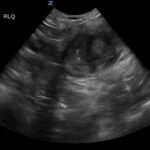

Small bowel diverticulitis is an uncommon subset of acute diverticulitis and can mimic many other intra-abdominal processes. As a result, imaging modalities such as ultrasound and computed tomography (CT) scan are especially important for timely recognition of diverticulitis and can expedite diagnosis and treatment and reduce complications. In the case described in this report, an 81-year-old male with history of esophageal cancer and recurrent diverticulitis with history of multiple bowel resections presented to the emergency department (ED) with right lower quadrant abdominal pain and constipation. Findings on ultrasound were suggestive of diverticulitis, and findings on CT of the abdomen and pelvis showed ileitis with phlegmon and micro-abscess suspicious for small bowel diverticulitis. ED providers should familiarize themselves with ultrasound findings of diverticulitis and be aware that diverticulitis can also present in the small bowel. Treatment of small bowel diverticulitis is similar to colonic diverticulitis.